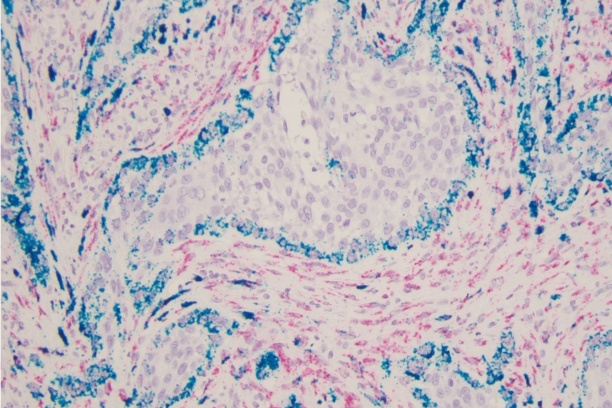

The Weiss laboratory is focused on understanding the molecular and immunologic mechanisms of thyroid cancer invasion and metastasis. While most thyroid cancer patients respond well to standard therapy, there are few options for those with widely metastatic or recurrent disease. Predicting which patients will have aggressive disease and treating those patients is an important goal in the field. The goal of the laboratory is to understand the signaling mechanisms and immune microenvironment responsible for the aggressive malignant behaviors of metastatic and recurrent disease. Projects include defining the role of Wnt signaling within the current molecular landscape of papillary thyroid carcinoma. The laboratory also uses computational immunogenomics to define the immunologic microenvironment within aggressive thyroid cancer subtypes to improve treatment and malignancy risk prediction at the time of biopsy.